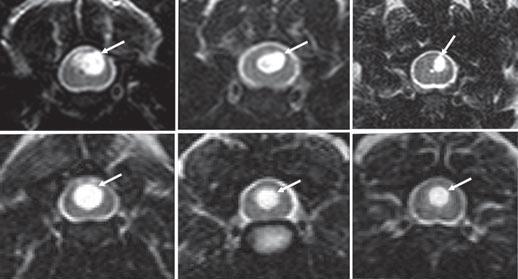

October 2021:

Syringomyelia "slosh" computer model shows how various syrinxes

may develop and expand in cavalier King Charles spaniels.

In an

October 2021 article, Drs. Srdjan Cirovic (right) and Clare Rusbridge,

both at the Univeristy of Surrey in the UK, report

on a computer model they devised which may explain how syringomyelia

(SM) syrinxes (syringes) are created and expand, due to the impulsive movement of

cerebrospinal fluid (CSF), called "slosh". A magnetic resonance imaging

(MRI) scan of a cavalier King Charles spaniel was used as the model

design for the study. The investigators conducted simulations of various

spinal cord conditions, from the cord being free of cavities to small

syringes at different locations to a prorgessively expanding syrinx.

(See Figure 2, below.) They found that, if small syringes are present, there are peaks of

stress at those locations, the effect being most pronounced at the

locations at which syringes initially form. When the syrinx reaches the

lumbar region, the stress becomes moderate. They concluded that their

findings support the "slosh" hypothesis, suggesting that small cervical

syringes may progress, but when the syrinx is large, there is less

stress, which may explain why a syrinx can rapidly expand but then

remain unchanged in shape over years. Their stated conclusions:

"The results of this study strongly suggest that the spinal cord tissue in the vicinity of fluid-filled cavities experiences higher than normal mechanical stress due to the movement of the CSF from epidural excitation. When the syringes are longer than approximately 30 mm, filling of the epidural veins may generate the "slosh" effect, where the fluid is forced to the caudal end of the syrinx. The results for the simulations of an expanding syrinx are broadly consistent with the homeostatic hypothesis, as the stress in the cord is lower for the fully developed syrinx than for smaller syringes. Other, potentially more realistic, scenarios for syrinx expansion should be examined in the future. This study specifically addresses syringomyelia in dogs, and more specifically in CKCS. ... Considering anatomical and other differences (e.g., upright posture in humans) the results regarding the potential pattern of syrinx enlargement do not apply to humans or to dog breeds other than CKCS."